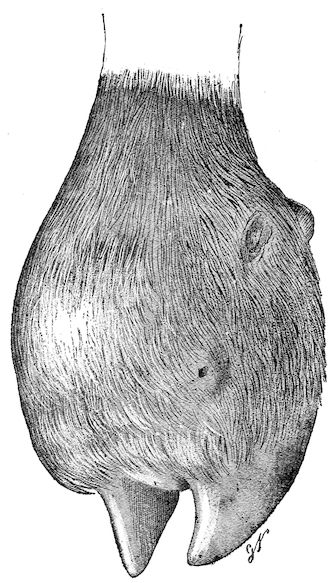

Fig. 3.—Pig suffering from osseous cachexia (fourth stage).

114. The fourth phase, or period of osteomalacia, i.e. softening of the bones, is also the last. It is rarely seen in large animals like horses and oxen, because accidents so often accompany the preceding stages and necessitate slaughter; but it is common in goats and pigs.

In this phase the bones become elastic, soft and depressible, yielding to the pressure of the operator’s fingers.

Fig. 4.—Deformity of the face in the horse shown in Fig. 2.

The flat bones are particularly liable to this change, which is common to domesticated animals. The bones of the head are the first to suffer; later those of the pelvis. The lower jaw becomes swollen, particularly about the centre of the branches which may attain three, four, or five times, their normal thickness.

The depression in the submaxillary space disappears. The upper jaw undergoes similar changes, becoming deformed and thickened until the cavities of the sinuses and the hollow appearance of the palate are lost, while the face is so changed that it cannot be recognised as that of a horse, goat, etc.

The molar teeth are almost buried, their tables alone being visible at the bottom of a depression, the edges of which rise above the neighbouring parts (pig).

Mastication is clearly impossible, the jaws appear paralysed, the muscles powerless, and only swallowing is possible, a fact which explains why life is only prolonged to this stage in animals which can be fed with a spoon or bottle (pigs and goats). The bones of the cranium, although greatly changed in texture, are always less deformed than those of the face.

The changes are such that it is often easy with a mere post-mortem knife to cut the head completely in two. Osseous tissue, properly so-called, has disappeared.

All the constituent tissues, with the exception of the skin and muscles, i.e., the bone, periosteum and aponeuroses, have the appearance and consistence on section of the fibro-lardaceous tissue seen in chronic inflammation.

Fig. 5.—Head of a pig suffering from osseous cachexia.

In the goat, the disease shows some slight peculiarities. Thus, in the second phase, during which goats and sheep suffer so markedly from lameness and pain in the bones, goats often walk on the knees. The disease, however, is uncommon in these animals. The phase of osteoclastia is also less marked and fractures are rare, because the animals weigh less and also because they are less exposed to falls and violent shocks. The bones, nevertheless, are extremely fragile and fractures may be produced at will.

Osteomalacia, on the other hand, is always well marked.

Regarding the development of the disease in pigs, we may repeat what has just been said respecting the goat. Walking on the knees is often one of the first signs, fractures are somewhat rare, and the period of softening and deformity is always very noticeable.